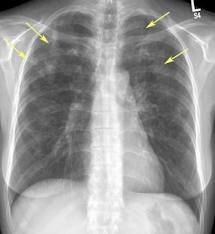

Эозинофильные инфильтраты

Эозинофильные инфильтраты являются состоянием аллергической природы, их причина появления не всегда может быть распознана. Такое заболевание может долго себя не проявлять либо сильно напоминать очаговую пневмонию. Иногда наблюдаются кашель, одышка, боли в груди, достаточно высокая температура.

Очаги легко определяются на рентгеновских снимках, они могут быть множественными либо одиночными, могут менять расположение. Читать далее